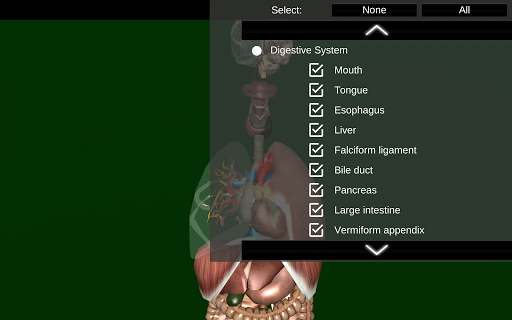

Internal Organs in 3D Anatomy لـ Vodafone Smart N9 Lite

Internal Organs 3D Anatomy 3.4

Internal Organs 3D Anatomy 3.1

Organs 3D Anatomy 2.0.12

يمكنك هنا تنزيل ملف حزمة تطبيق أندرويد "Internal Organs 3D Anatomy" الخاصة بجهازVodafone Smart N9 Lite مجانًا، نسخة ملف حزمة تطبيق أندرويد - 3.4 للتحميل على Vodafone Smart N9 Lite اضغط ببساطة على هذا الزر. إنه سهل وآمن. نحن نقدم فقط ملفات حزمة تطبيق أندرويد الأصلية. إذا انتهكت أية مواد موجودة في الموقع حقوقك قم بإبلاغنا من خلال